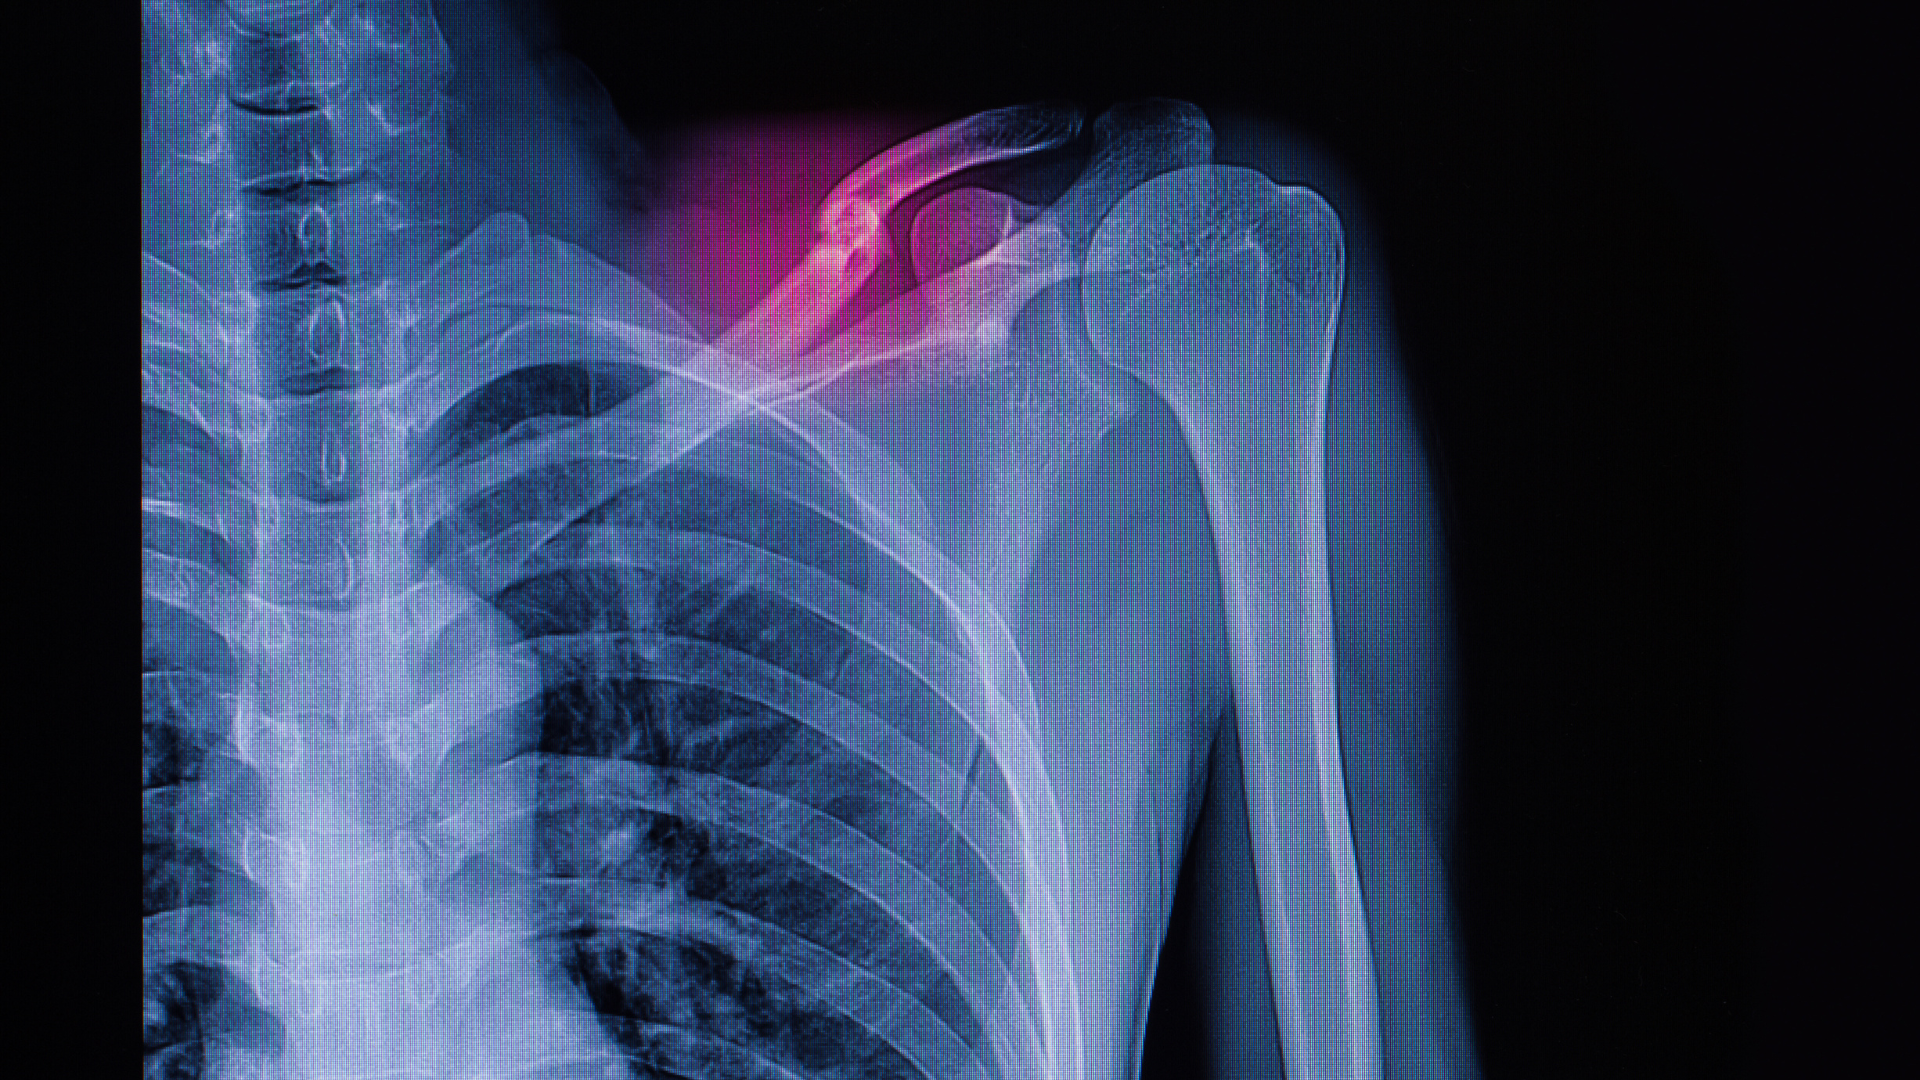

- Chụp X-quang xương đòn: Đây là phương pháp chẩn đoán hình ảnh tiêu chuẩn vàng. Phim X-quang thẳng và phim chếch 45 độ giúp bác sĩ xác định chính xác vị trí gãy, đường gãy (gãy ngang, gãy chéo hay gãy vụn) và mức độ di lệch của các đoạn xương.

- Chụp cắt lớp vi tính (CT Scan): Thường chỉ được chỉ định trong các trường hợp gãy phức tạp ở hai đầu xương đòn có liên quan đến khớp ức đòn hoặc khớp cùng đòn, hoặc khi nghi ngờ có tổn thương các tạng trong lồng ngực mà X-quang không quan sát rõ.